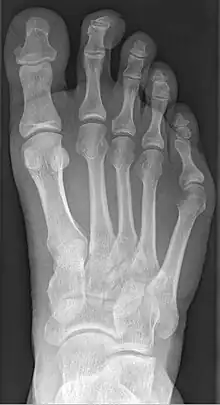

Radiograph showing a tailor's bunion | |

Tailor's bunion is easily diagnosed because the protrusion is visually apparent. X-rays may be ordered to help the surgeon find out the severity of the deformity.